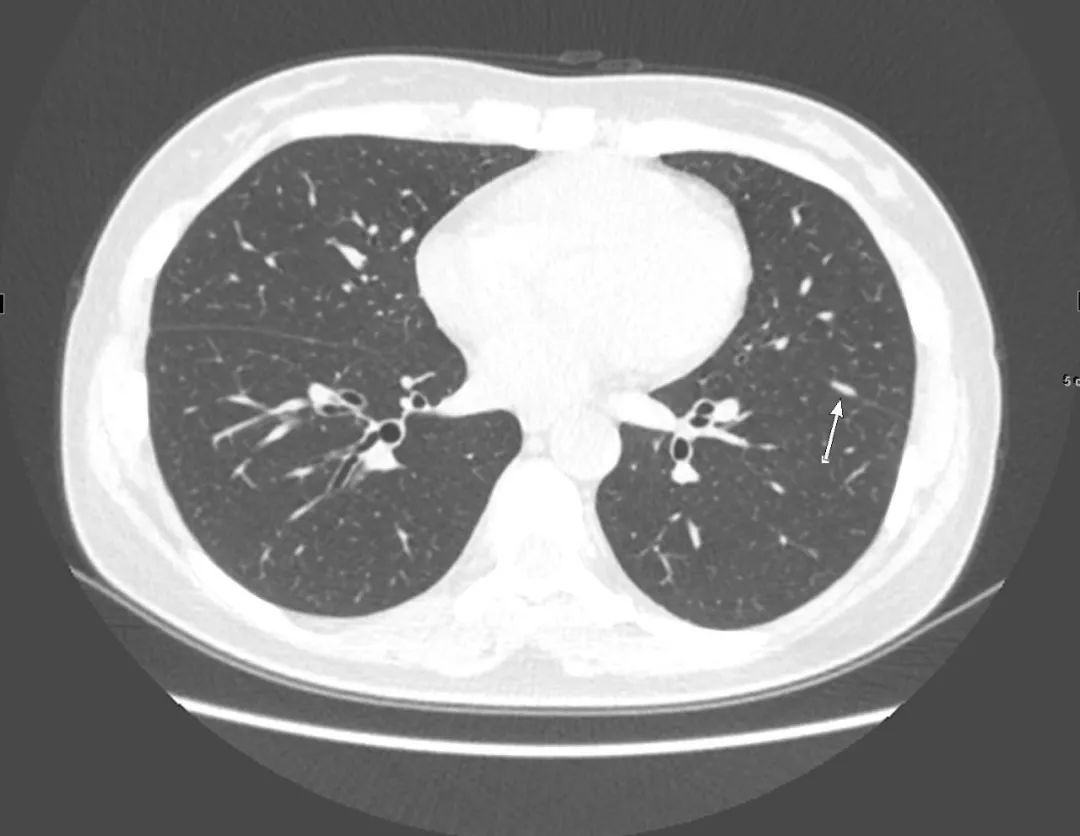

患者的腰椎间盘突出不是严重,之所以将患者家属喊来询问病史,是因为看到了腹主动脉血管壁钙化,确切的说是“不一样”血管壁钙化,腹主动脉(双肾下极水平以下)内分隔影伴钙化(如下图):

正常情况下,老年人血管壁有钙化是再正常不过,但钙化即使再严重,也是呈环形贴着血管壁,上面这样钙化很怪异,分隔伴细条状钙化。如果没有任何症状,可能是正常的;但当有症状时,而且腰痛用正常的腰椎间盘突出难以解释时,不能除外一种相对少见但非常危险的情况——“主动脉夹层”。